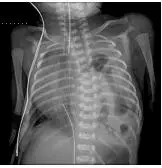

一名體重約 2.5公斤的女嬰,出生時有呼吸窘迫、腹部凹陷的現象。 X光檢查發現在左側胸腔內充滿腸氣(如圖)。下列敘述何者錯誤? 圖片描述

從胸部 X 光可見左側胸腔大量彎曲、透亮的氣影,形狀與腸袢相符;左肺野肺容積減少,心臟與縱隔明顯向右側移位;腹部呈凹陷(scaphoid abdomen),肋間收縮加劇。這些影像特徵高度符合同步呼吸窘迫的新生兒 CDH,顯示腹腔內容物已經自橫膈缺損處進入左胸腔,壓迫左肺並造成肺發育不良。